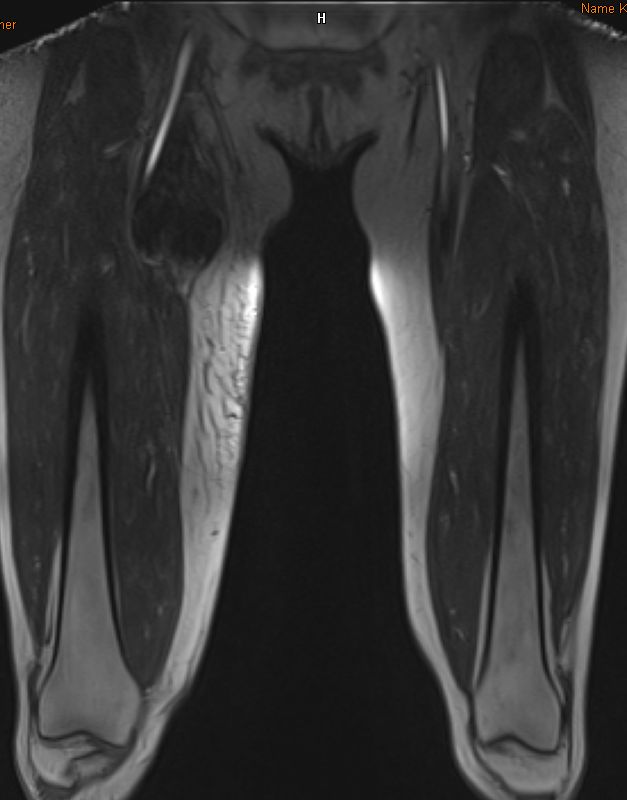

| Oberschenkel | 49-jährige Frau mit einem myxoiden Liposarkom der rechten Adduktoren-Loge.![]() |

Die enge Lagebeziehung zur A. femoralis ist gut erkennbar.![]() ![]() |

Frontale Schnittrichtung